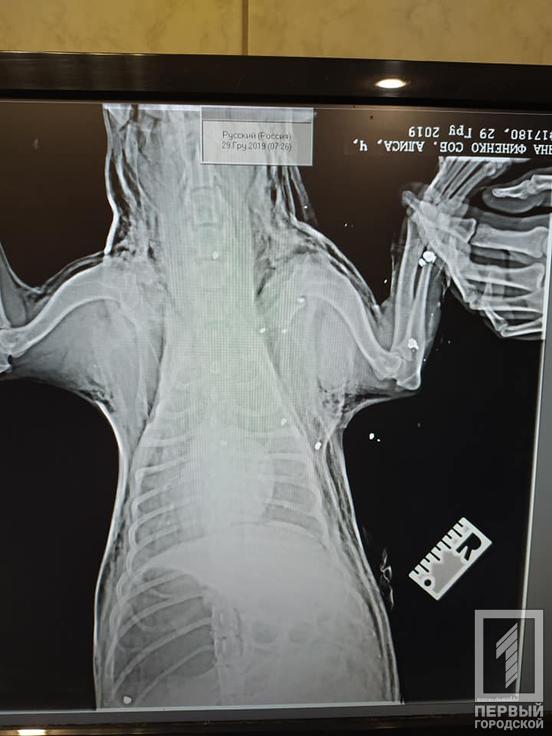

Также собаке сделали рентген, по словам девушки, на нём видно, что собаку не просто порезали, а расстреляли.

«На рентгене хорошо видно, что это не порезы, а собаку расстреляли. За что? За что этой малышке такое?», - недоумевает волонтёр.